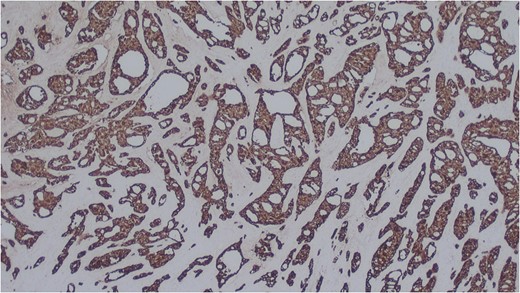

Histology of the mass confirmed sinonasal SDC. Tissue specimens showed cellular stroma extensively infiltrated by carcinoma composed of large eosinophilic cells with gland formation (Fig. 2). Widespread nuclear pleomorphism was evident. The sample was positive for cytokeratin-7 (CK7) (Fig. 3), epithelial membrane antigen (EMA), BerEP4 and demonstrated focal positivity for cytokeratin-5/6 (CK5/6). Post-operative MRI scans were requested to rule out residual disease or cervical lymphadenopathy (Fig. 4). Following review by Regional Head and Neck Cancer multi-disciplinary team and the oncologist, the patient was treated with a radical course of radiotherapy which was completed without complications. The patient has been reviewed regularly in the Head and Neck Cancer clinic with no evidence of recurrence at 18 months.

Cellular stroma extensively infiltrated by carcinoma composed of large eosinophilic cells with gland formation on medium power view. Haemotoxylin and eosin (H&E).